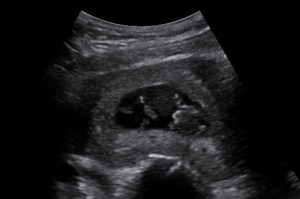

As of right now I am at 12 weeks gestation, so I’m nearing the end of the first trimester. It has already gone by so fast. When I first found out I was pregnant, my baby was the size of a poppy seed, and now it’s the size of a plum! Pretty crazy!

“Baby Howie” (as my friends lovingly call him/her) is due July 21st. (Yes, I am aware it is going to be hot in Arizona in July.) I have yet to figure out how I will manage maternity leave and rotations, but hopefully my school is supportive. I know I’m not the first student to get pregnant, so they are probably familiar with this sort of thing.